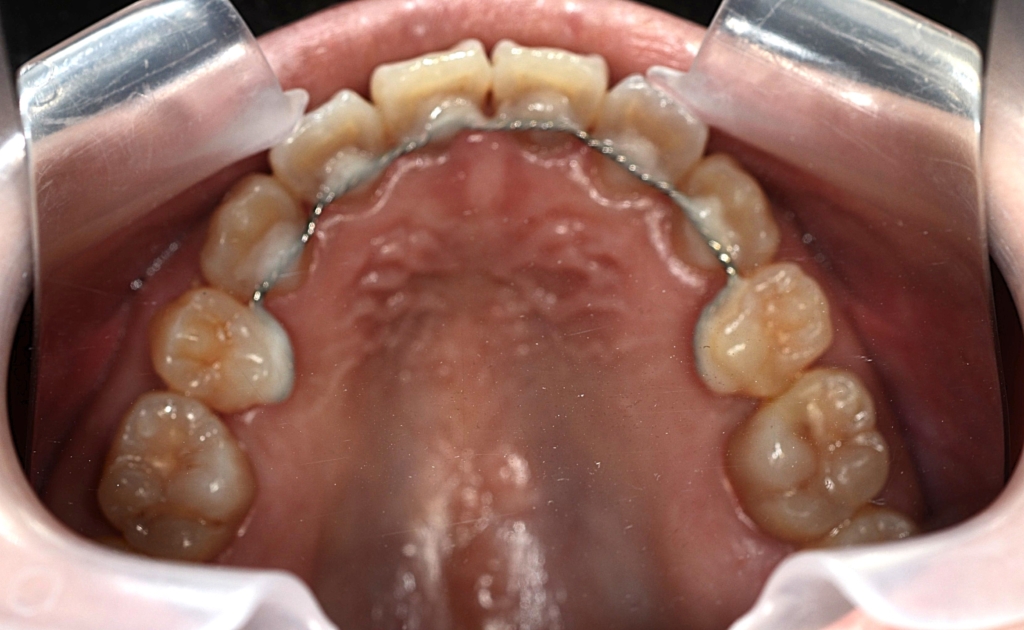

予定通り上顎の口蓋にアンカースクリューを植立しました。

あらためて上顎に、「PLAS」と「パラタルバー」を装着して、上の歯列全体を後方へ押して引っ込めて行きます。

【保定】 上下ともフィックスタイプ&クリアリテーナー